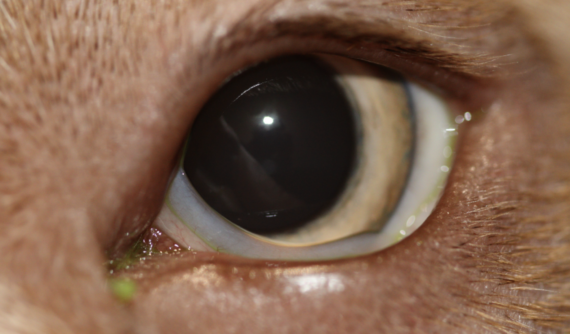

Durante el examen, se inspecciona minuciosamente el borde del párpado en busca de la presencia de pelos anormales que puedan indicar la existencia de un cilio ectópico. Este proceso generalmente requiere el uso de un microscopio ocular conocido como lámpara de hendidura.

Para evaluar posibles lesiones corneales causadas por el roce continuo del cilio ectópico, se realiza una tinción con fluoresceína. Esta técnica implica la aplicación de una solución de fluoresceína en el ojo, lo que revela cualquier daño en la superficie corneal al mostrar áreas teñidas de color verde brillante bajo una luz especial. Mediante esta prueba, confirmamos la presencia de una úlcera superficial en el ojo derecho de la paciente.

Las úlceras son como pequeñas heridas en la superficie del ojo que pueden resultar muy dolorosas y causar molestias significativas. En este caso, la úlcera fue causada por un cilio ectópico en el párpado superior.